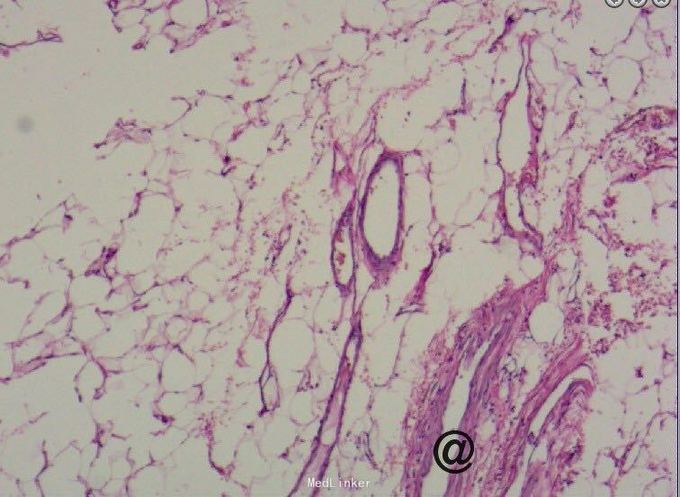

请妇科会诊,该科医师行妇检未见明显包块,且CA125正常,建议行小肠检查,同时行彩超探查了解包块来源,妇科彩超:子宫较小,宫体后壁肌壁间肌瘤(稍凸向宫腔),右侧附件区实质性包块,考虑为右侧卵巢肿瘤,左侧附件区未见明显异常显示,盆腔未见明显积液。 请妇科商议并于患者沟通后于2015.10.08转入妇科,转科行积极完善术前准备,于10.16行剖腹探查术。术中见:子宫稍大,质硬,后壁与直肠致密粘连,左侧卵巢大小正常,右侧卵巢增大直径约4cm,双侧附件与子宫后壁及盆壁致密粘连,分离盆腔粘连后可见巧克力样液体,阑尾可见约9*5*4cm肿瘤,包膜完整,与周围组织无粘连。请胃肠外科主任上台会诊,行阑尾切除术,术中快速病理切片检查示:(阑尾)腺上皮高级别上皮内瘤变(腺上皮中-重度异型增生),确诊待常规。再次向家属交代病情,将快切结果告知患者家属,患者家属了解病情,要求切除右半结肠,切除全子宫及双侧附件,最终行:全麻插管下行右半结肠根治性切除+肠粘连松解+腹式全子宫切除+双侧卵巢输卵管切除术。术后病检提示:(阑尾)中分化腺癌,癌浸润达肌层。阑尾手术切缘未见癌组织。免疫组化:CK19(+),Ki-67 LI约60%。子宫附件及右半结肠:1.送检肠管粘膜组织呈慢性炎,粘膜下水肿,纤维脂肪组织增生,血管扩张、充血。肠周触及淋巴结13枚呈反应性增生。 2.子宫腺肌症,囊性萎缩性子宫内膜组织,慢性子宫颈炎伴鳞状上皮化生。 3.(双侧)卵巢白体形成,(右侧)符合子宫内膜异位囊肿;(双侧)输卵管组织呈慢性炎,(右侧)伴系膜囊肿。